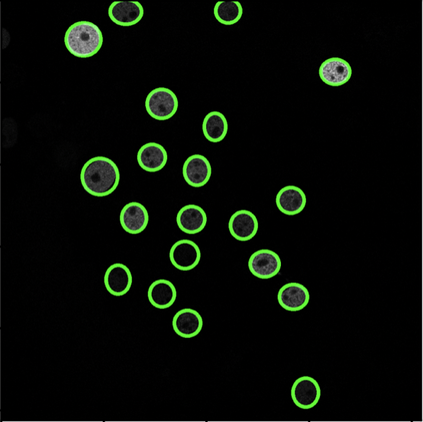

Cell detection in microscopy images is important to study how cells move and interact with their environment. Most recent deep learning-based methods for cell detection use convolutional neural networks (CNNs). However, inspired by the success in other computer vision applications, vision transformers (ViTs) are also used for this purpose. We propose a novel hybrid CNN-ViT model for cell detection in microscopy images to exploit the advantages of both types of deep learning models. We employ an efficient CNN, that was pre-trained on the ImageNet dataset, to extract image features and utilize transfer learning to reduce the amount of required training data. Extracted image features are further processed by a combination of convolutional and transformer layers, so that the convolutional layers can focus on local information and the transformer layers on global information. Our centroid-based cell detection method represents cells as ellipses and is end-to-end trainable. Furthermore, we show that our proposed model can outperform fully convolutional one-stage detectors on four different 2D microscopy datasets. Code is available at: https://github.com/roydenwa/cell-centroid-former